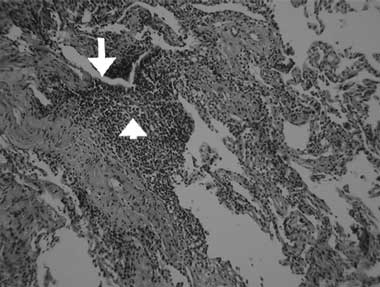

A computed tomography (CT) scan of the chest showed inhomogeneous opacities, as well as dilated airways crowded in the medial segment of the right middle lobe and inferior segment of the lingula, without mediastinal lymphadenopathy (Box, B). A fibrobronchoscopic examination to verify central bronchial patency showed no intraluminal obstruction in the affected bronchi. Cultures of the lavaged bronchial fluid were negative for tuberculosis and other microorganisms, and no malignant cells were found in aspirated specimens. A transbronchial biopsy from the atelectatic middle lobe revealed lymphocytic bronchiolitis with a moderate degree of mononuclear cell infiltration, predominantly by lymphocytes, in the terminal bronchiolar walls and adjacent interstitial areas, and no granuloma formation (Box, C).

With pulmonary involvement in primary Sjögren’s syndrome, the inflammation can be focal and predominantly cellular, with lymphocytes infiltrating the small airway walls.7,8 Local bronchial or bronchiolar lymphocyte infiltrates and inflammatory cell products may lead to impairment of tracheobronchial mucociliary clearance.8,9 In our patient, lymphocytic infiltrations in the terminal bronchioles were found in the atelectasis of the right middle lobe and lingula. The atelectatic and bronchiectatic lesions seen on the chest CT scan resolved after immunosuppressive drug treatment. Lymphocytic bronchiolitis with underlying bronchiectasis has also been described in patients with non-obstructive middle lobe syndrome.